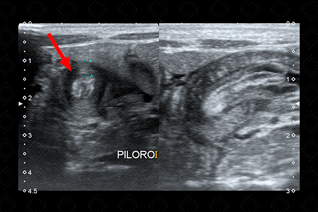

Texto alternativo para a imagem Figura 1. Créditos: Dra. Elazir Mota - Rio de Janeiro/RJ

Descrição da figura 1: Ultrassonografia do abdome - estudo destinado à avaliação do piloro, evidencia o canal pilórico alongado, medindo 20 mm (o comprimento normal do piloro é ≤ 12-16 mm) e a camada muscular hipertrofiada, com sua espessura de 4 mm (a espessura normal da camada muscular é ≤ 3 mm).

Descrição das figuras 2 e 3: Ultrassonografia do abdome de lactente com 27 dias de vida evidenciando muscular do piloro espessado (sua muscular media 4 mm) e o canal pilórico alongado. Observe a aparência em alvo do piloro no seu corte transversal, outro sinal clássico de EHP (seta vermelha).